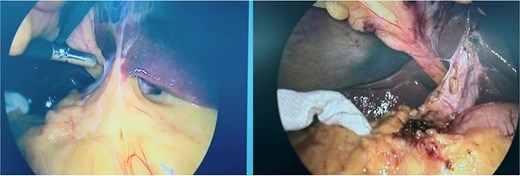

The procedure was initiated using our routine three-port technique, including a 10-mm umbilical camera port, a 10-mm epigastric working port, and a 5-mm right subcostal port. Upon laparoscopic exploration, the gallbladder was unexpectedly identified to the left of the round ligament (Figs 2 and 3a). To facilitate adequate exposure and safe dissection, the epigastric trocar was repositioned to the left side (Fig. 3b). The gallbladder was mildly inflamed and adherent to the omentum. After repositioning of the epigastric trocar, meticulous dissection was performed and the Critical View of Safety was fully achieved before clipping and division of the cystic duct and artery. No bailout strategy such as fundus-first dissection or subtotal cholecystectomy was considered necessary, and intraoperative cholangiography was not required because the biliary anatomy was clearly identified. The operative time was 70 minutes, and the procedure was completed without intraoperative complications. The postoperative course was uneventful and the patient was discharged on postoperative day two. He returned to work on postoperative day five.

The greater omentum adherent to the inflamed gallbladder, shown before and after adhesiolysis.

Intraoperatively, the gallbladder was found entirely to the left of the round ligament without situs inversus (a). The epigastric trocar was repositioned to the left of the falciform ligament to improve exposure and facilitate dissection (b).